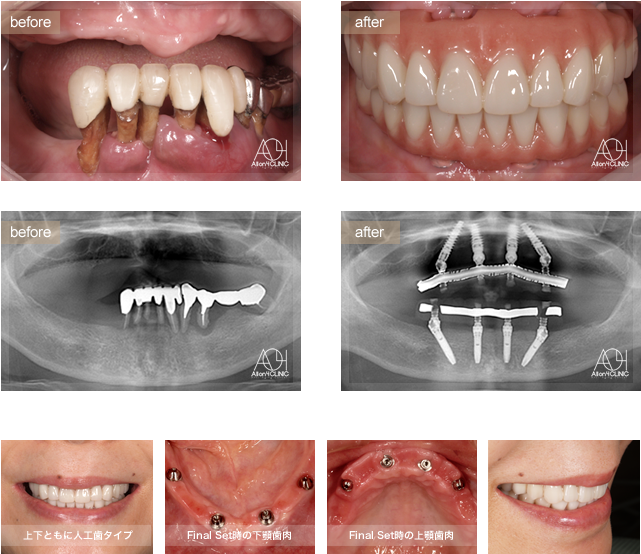

Age : 61

Sex : Female

Treatment :

- Maxilla All-on-4

- Under All-on-4

上下All-on-4。上下ともに人工歯タイプ。